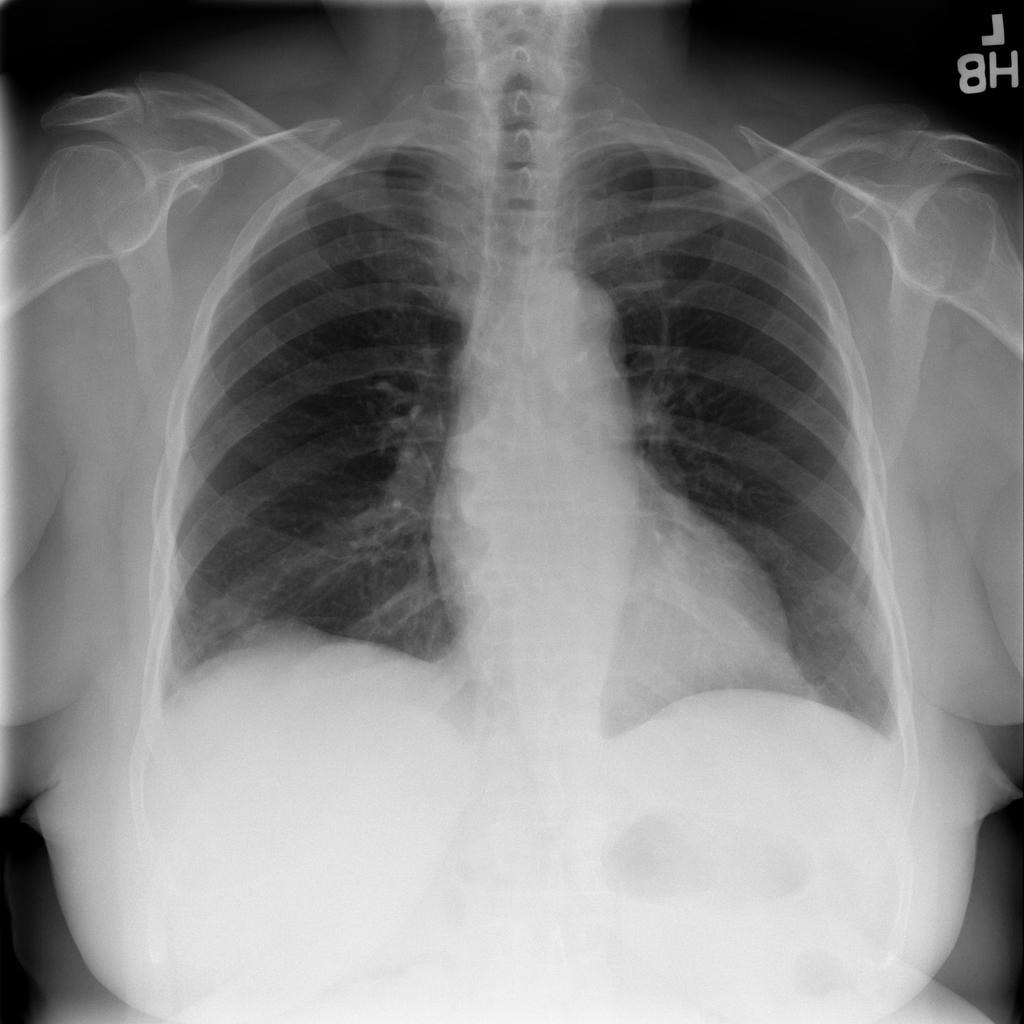

Showing up to 90 reference images for Hernia.

PAT-4F7E · IMG-000Hernia

PAT-4F7E · IMG-000

PA